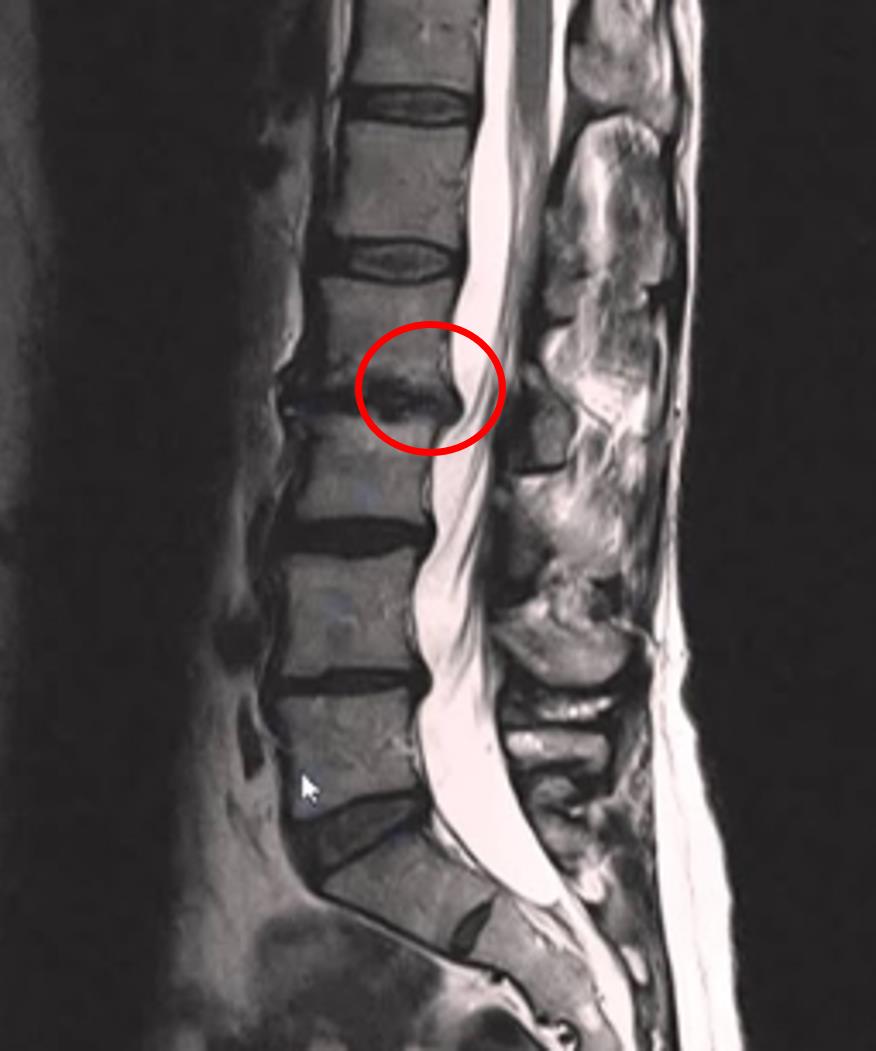

A 53-year-old woman presents to her primary care physician with a 1 month history of low back pain. The pain started after she visited her daughter to help her move into her college dorm. Since then, the pain has improved slightly over time but it continues to bother her with lifting and bending activities. She also notes pain that occasionally goes down her left leg to the thigh. She denies any changes in bowel or bladder function. She has not noticed any pain in the middle of the night. She has not tried any treatments yet for this pain. Her medical history is significant for obesity, type 2 diabetes, and GERD for which she takes metformin and omeprazole. Her temperature is 98.6°F (37°C), blood pressure is 131/84 mmHg, pulse is 92/min, and respirations are 14/min. On a physical exam, pain is elicited upon palpation of the patient's lower back. Flexion of the patient's thigh results in pain that travels down the patient's lower extremity to the medial thigh. An MRI is obtained with the results shown in Figure A. Which of the following is the most appropriate next step in management?

Figure/Illustration A is an MRI demonstrating a herniated disc (red circle). There is no compression of the cauda equina at this level so there is not likely to be complicating factors.